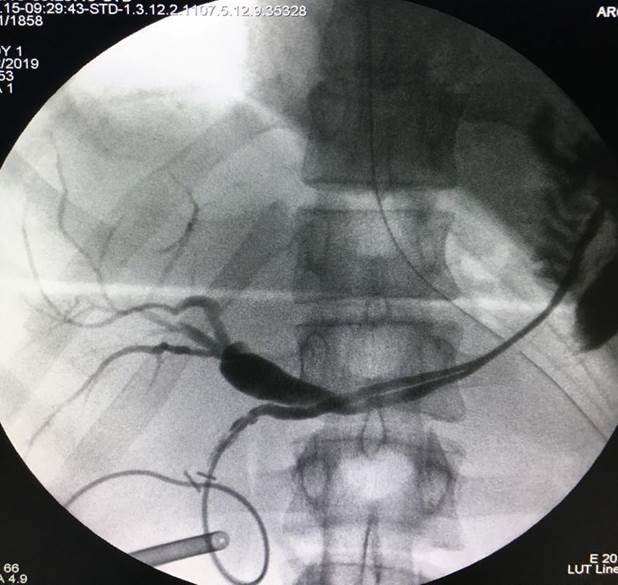

Anatomical alterations of the main bile duct of mechanical etiology as findings during intraoperative cholangiography

Two intraoperative cholangiographies performed in the context of coordinated laparoscopic cholecystectomies are presented.